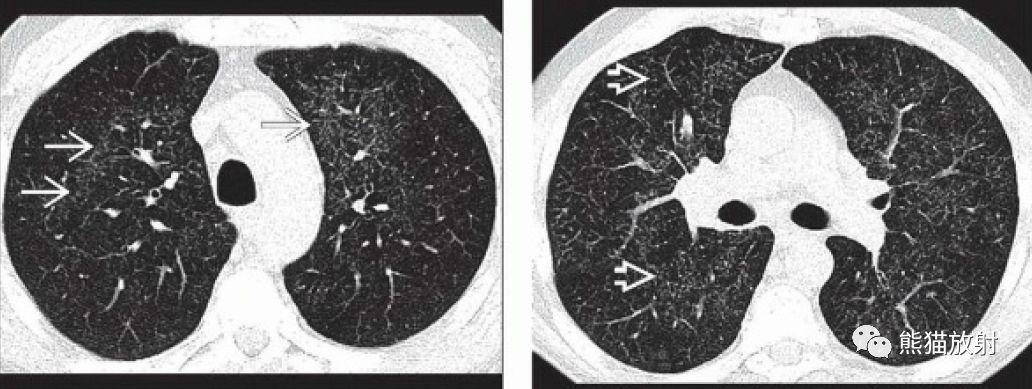

病毒性肺炎丨ct表现,诊断要点_小叶

病例 :男 岁患者,另一例小叶性肺炎.